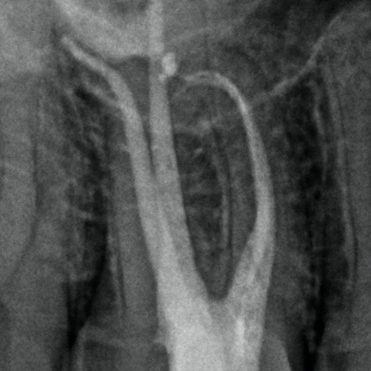

Figure 1: MB1 and MB2 are two separate canals.

- Preoperative radiograph

- Mid-fill radiograph showing MB1 and MB2 are completely separate canals with individual apical foramen; both canals have acute apical curvatures

- Postoperative radiograph; a lateral canal was noted in the palatal canal.